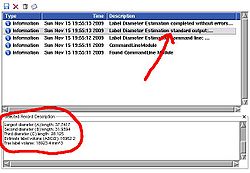

The module also outputs numeric values for the lengths of the computed diameters. To see these numbers, open Log Viewer, and select the first from top log record with the name Label Diameter Estimation: standard output. The reported numbers are the lenghts of the three diameters, the volume estimate calculated as A*B*C/2 (a formula suggested in the literature for estimating volume of hematomas from planimetric measurements [2]), and the true label volume in mm^3. |